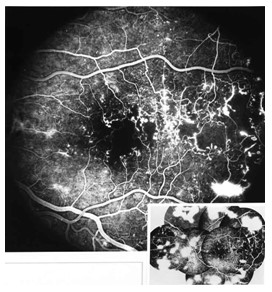

b. Fundus Fluorescein Angiography

This diagnostic procedure utilizes a specialized fundus camera or scanning laser ophthalmoscope to capture rapid-sequence photographs of the retina following an intravenous injection of fluorescein sodium. Photographic or video images taken as the dye courses through the eye can demonstrate abnormalities within the neurosensory retina, pigment epithelium, sclera, choroid, and optic nerve, providing clinically useful information for nearly the entire spectrum of posterior segment disorders.

DR 1 DR 2